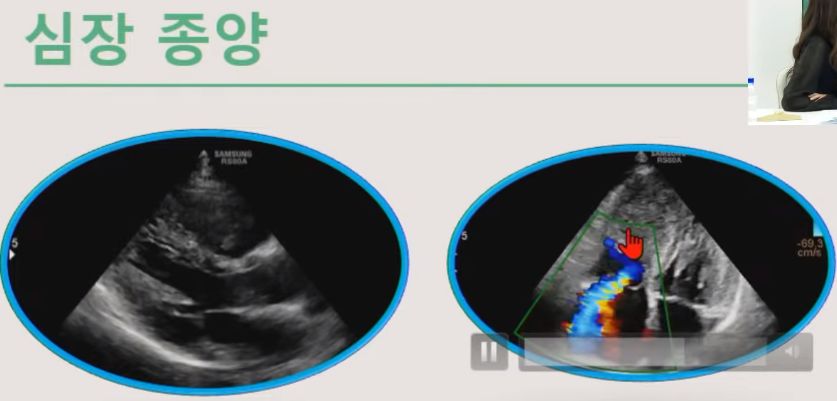

ㅡ 심장초음파검사로 심장크기, (심장벽)두께 측정, 심장기능 평가, 판막질환 진단 및 평가, 선천성 심장질환 진단, 심낭 삼출, 심장종양 진단.

심장 종양, 심낭 삼출

ㅡ 심장초음파 검사는 심장의 구조와 기능을 평가.

ㅡ 도플러 초음파를 이용하여 혈역학적 평가 가능.

ㅡ 심장질환의 정확한 진단, 치료방침과 예후를 평가하는 저렴하고 쉽게 적용할 수 있는 중요한 비침습 검사법.

* 실제 영상을 보세요. 각 경우를 동영상으로 보여줍니다.